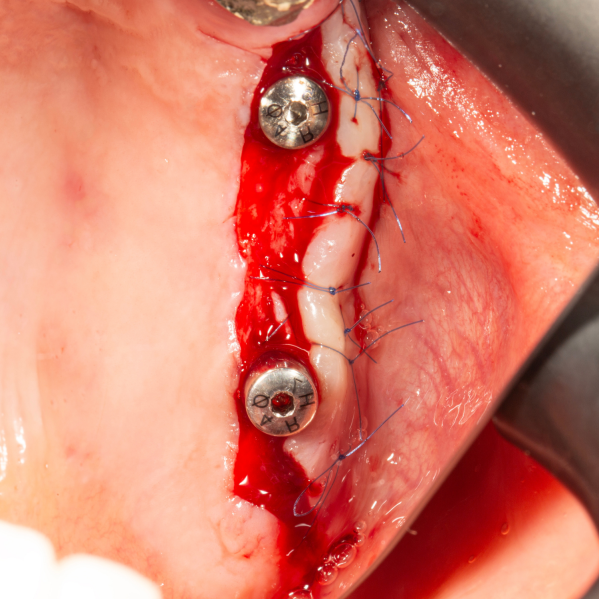

İmplant etrafındaki kemik açıklığını kemik grefti ile tedavi ettiğimiz vakamız.